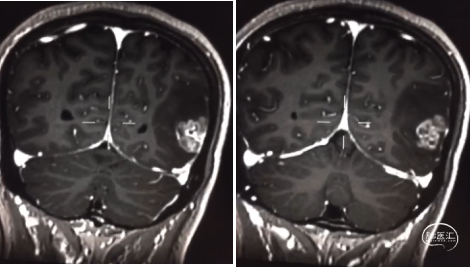

患者为中年男性,因“间断性头痛2月,加重1周”于2020年4月30日入院。入院时神经系统体征(-)。术前诊断为左顶枕叶胶质瘤。